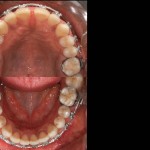

Foto e documentazione